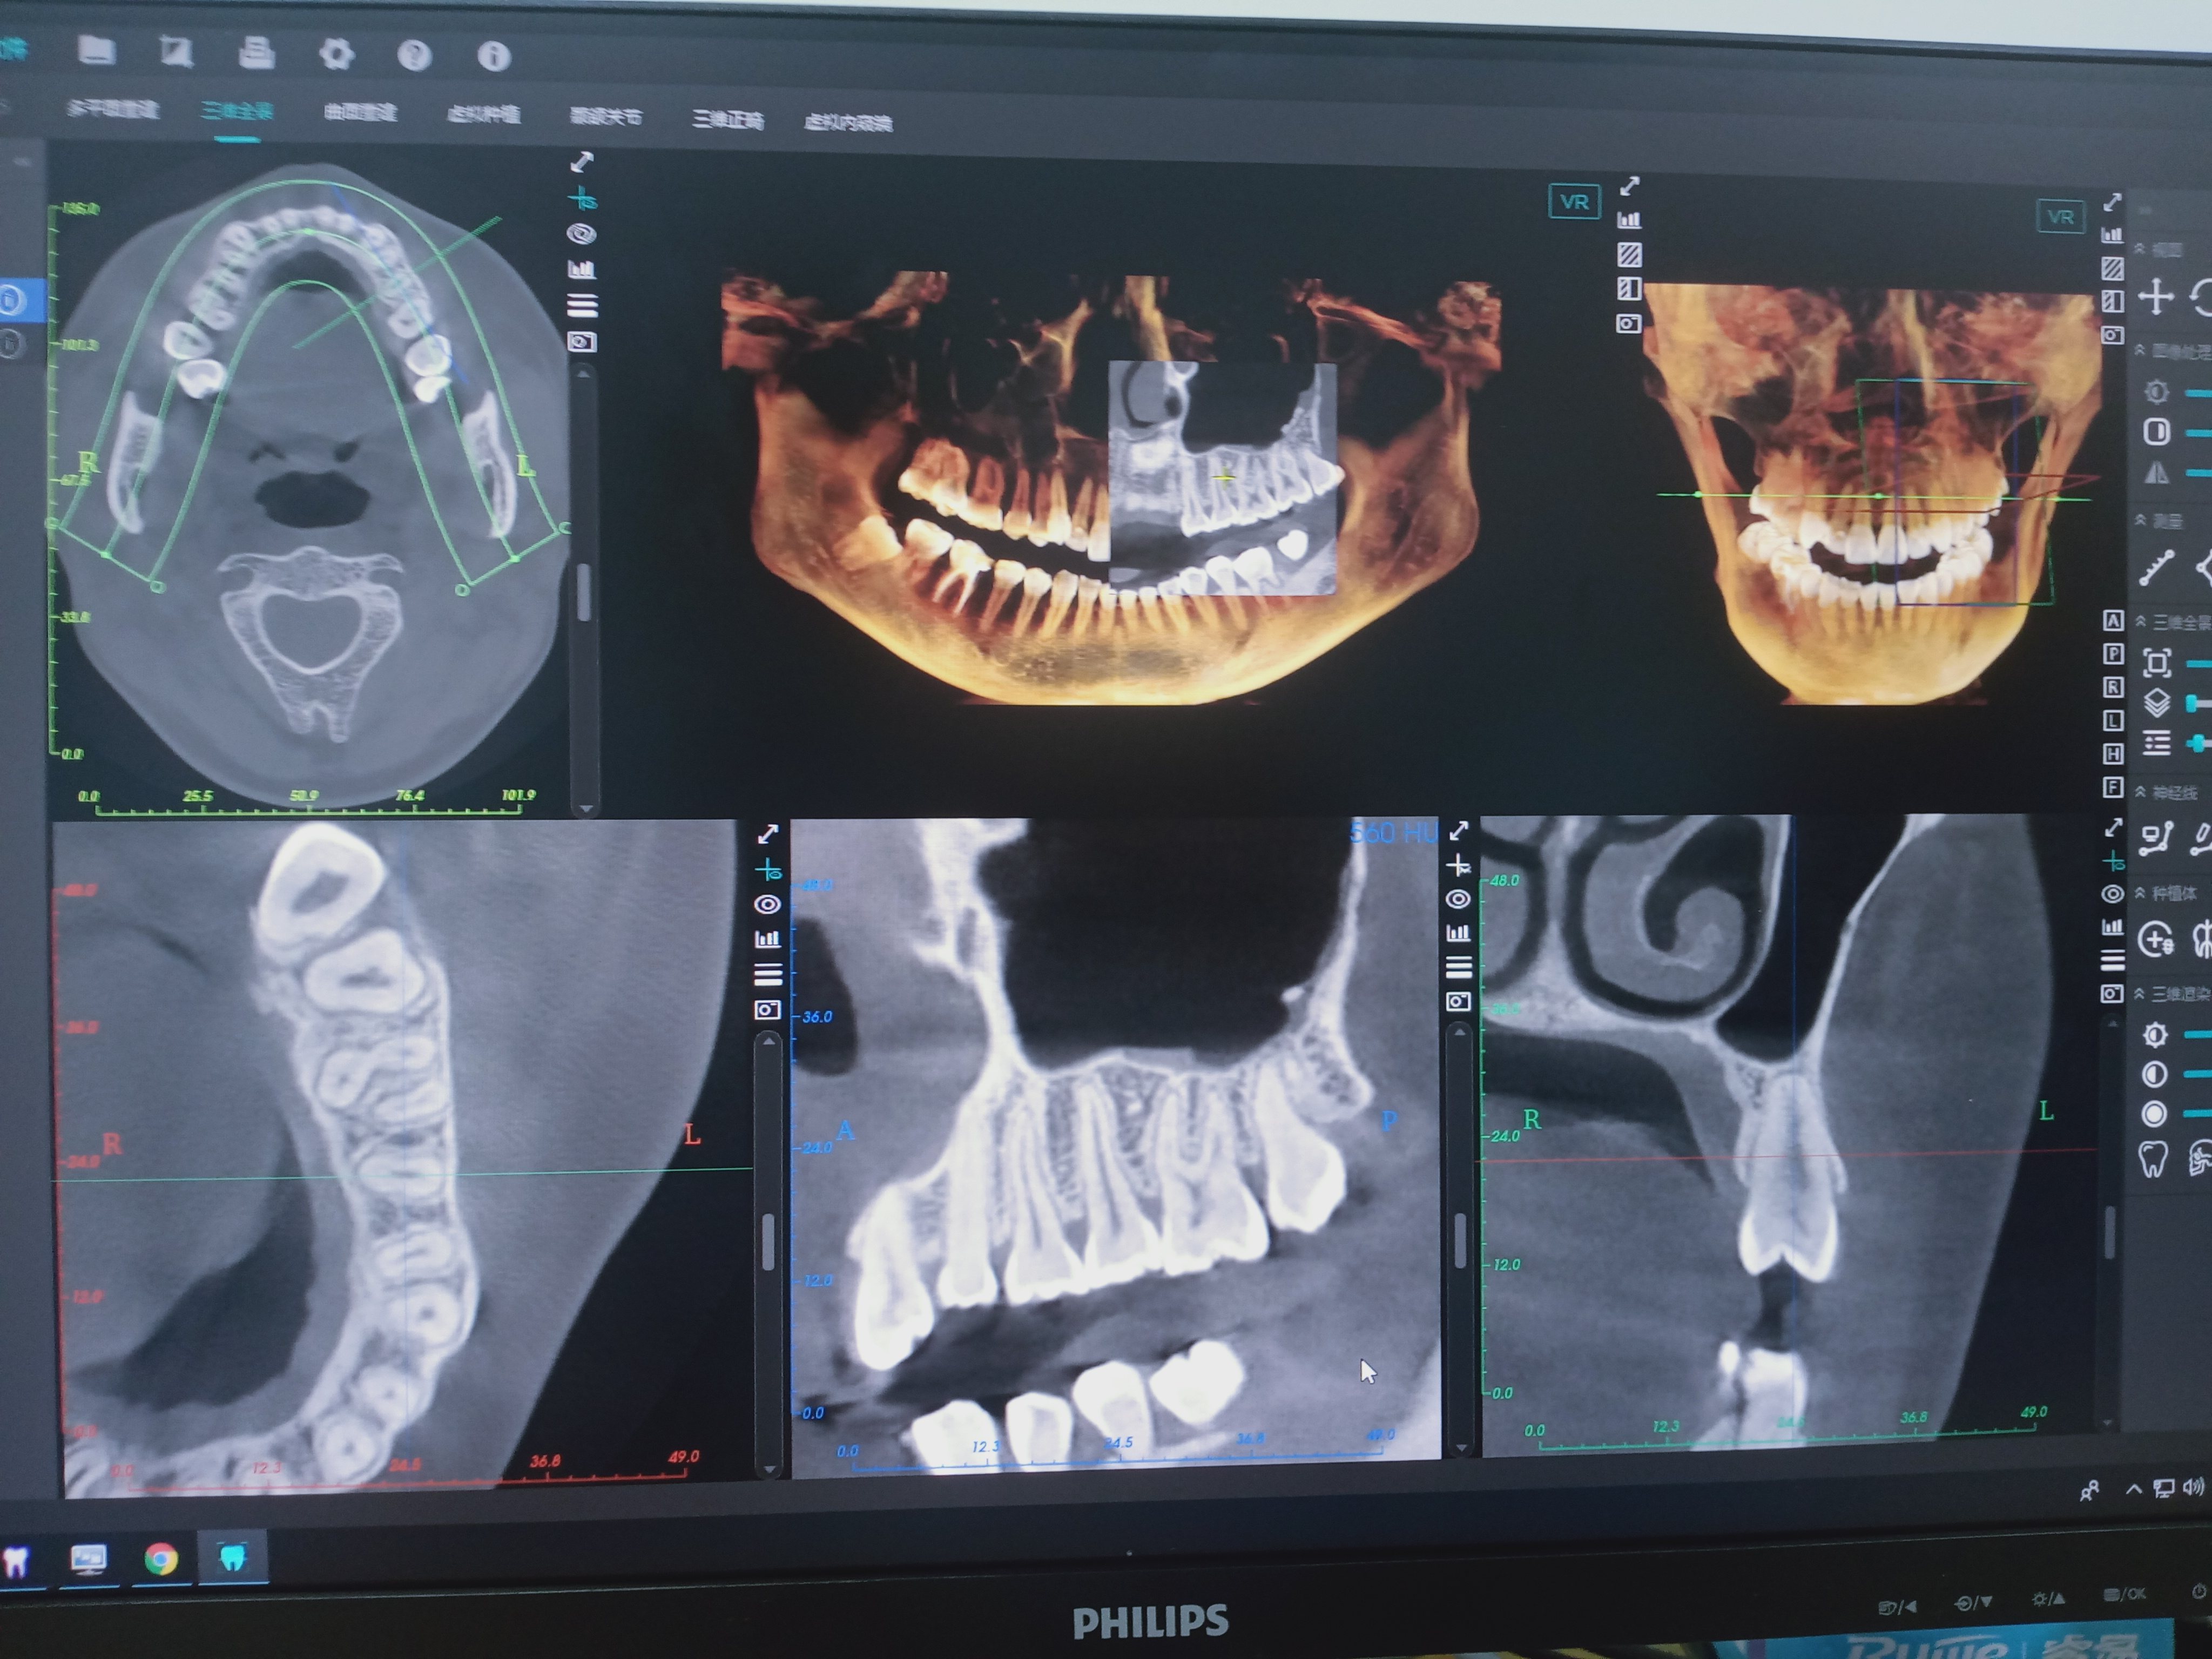

2、口腔CT(锥形束CT):可从三维角度对组织情况进行反映,准确清晰地诊查各组织的健康状态,病损范围及与周围组织间的关系以及发现更加细微的病变,诊查各类阻生牙的位置状态及与临近的神经和窦腔的位置距离,协助医师们在进行术前方案设计以及术后科学评价,还可清晰地检查牙槽骨内的病损。